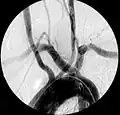

Aberrant subclavian artery on MR angiography.

Magnetic Resonance Imaging (MRI): MRI or MR angiography can similarly detail the vascular anatomy and is often used in children to reduce radiation exposure.